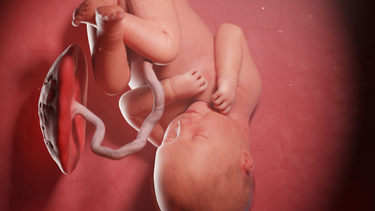

Tháng thứ 3 của thai kỳ là giai đoạn cơ thể người mẹ có nhiều thay đổi mạnh mẽ về nội tiết, cấu trúc tử cung và hệ tiêu hóa. Việc hiểu rõ nguyên nhân gây đau bụng âm ỉ, phân biệt đâu là biểu hiện bình thường và đâu là dấu hiệu bất thường sẽ giúp mẹ bầu chủ động bảo vệ sức khỏe của bản thân và thai nhi, tránh lo lắng không cần thiết nhưng cũng không bỏ sót nguy cơ.

Căng giãn dây chằng tử cung

Khi thai nhi phát triển, tử cung lớn dần khiến các dây chằng nâng đỡ tử cung bị kéo giãn. Điều này có thể gây đau âm ỉ hoặc đau nhói nhẹ vùng bụng dưới, bẹn hoặc một bên bụng. Đây là nguyên nhân sinh lý phổ biến trong tam cá nguyệt đầu và giữa thai kỳ, đặc biệt khi: